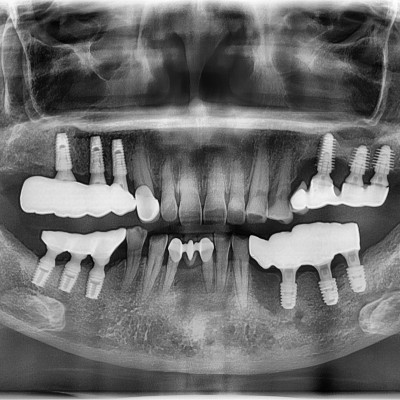

임플란트 재수술 #14.15.16.17 타원 임플란트 제거 후 임플란트 식립+ 치조골 이식술 시행하였습니다.